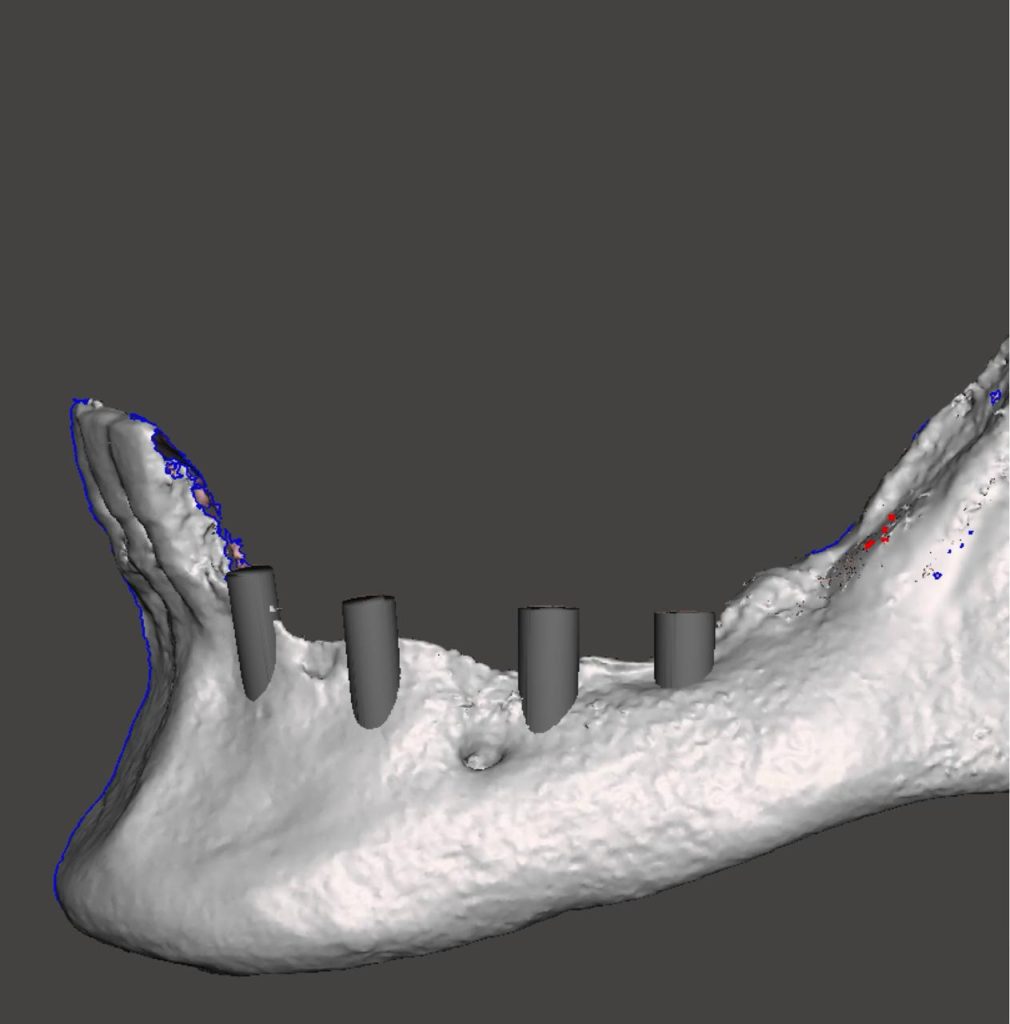

- Presentazione e discussione della griglia decisionale della GBR

- Mesh customizzate di nuova generazione: campi d’applicazione, potenzialità, strategia di fissaggio, prospettive e futuro, modalità di rimozione

- One Stage Vs Two Stages: scelta della procedura in funzione del criterio biologico e, per i settori anteriori, delle esigenze estetiche

- One Stage Vs Two Stages: casi clinici esemplificativi dell’applicazione dell’una o dell’altra procedura